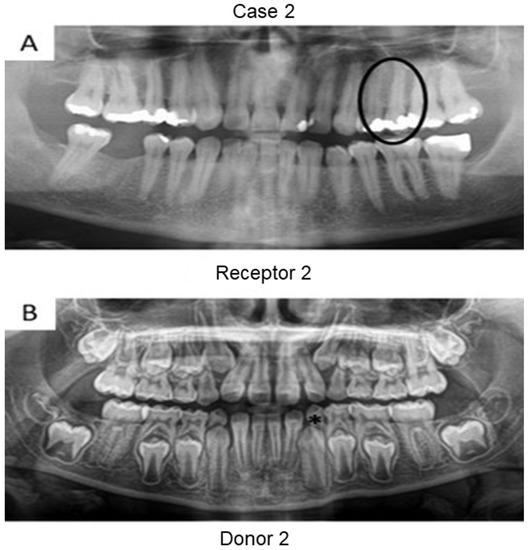

First, panoramic radiography was performed on all patients in the three cases (Figure 1, Figure 2 and Figure 3), as well as computed tomography (CT) scanning with a 0.25 mm voxel size in order to confirm the periapical status of each tooth requiring endodontic treatment. The extraction of teeth from the patients’ children was performed without tooth sectioning and with extreme caution in order to avoid damaging the tooth and the apical structures. The extraction was carried out with local anesthesia using 1.8 mL of 2% lidocaine (1:80,000 epinephrine) through a nerve block technique. The extracted teeth were stored in a sterilized saline solution. At the same time and in the same dental office, the single-root teeth requiring root canal treatment were also anesthetized as aforementioned, isolated with a rubber dam, and pulp chamber access was executed with diamond burs with a high-speed handpiece under continuous and copious water irrigation. The canal instrumentation was performed using rotary files (Wave One Gold, Dentsply, Rio de Janeiro, Brazil) in combination with irrigation using a tri-antibiotic solution (ciprofloxacin, minocycline, and metronidazole at 500 μg/mL each) [14,15]. Prior to the rotary files, one #10 manual K-file (Dentsply) was used to perform the patency. No apical bleeding was performed because it was a different protocol than the revascularization strategy [15,16].

Herein, the primary teeth extracted (asterisks in Figure 1 and Figure 2) were scheduled to be extracted with minimal injury as they were vertically inclined, and permanent teeth were already formed/erupted in cases 1 and 2. Furthermore, the tooth must be stored as soon as possible in a sterilized saline solution; the complete disinfection prior to pulp removal and transplantation is mandatory [21]. The sectioning of the extracted tooth must be performed using a sterilized handpiece and diamond disks only after the root canal instrumentation of the receptor tooth [10]. Pulp should also be removed with sterilized tweezers (Figure 4B) and inserted into the roots of the acceptor teeth using disinfected gutta-percha cones. Indeed, all these procedures may promote minimal contamination during the clinical treatment, thereby increasing the probability to perform bacterial-free endodontic regeneration.

Figure 2. Panoramic radiographs of initial visit of the two patients in case 2. Black circle indicates the tooth requiring root canal treatment (receptor tooth) in the father whilst the asterisk points to the primary canine of the patient’s daughter planned for extraction (pulp donator tooth).